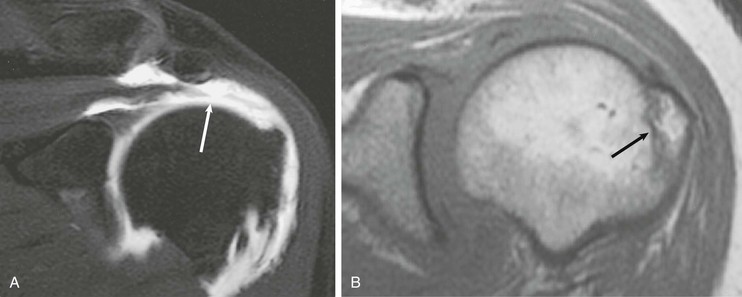

Although conventional MRI is established as the imaging modality of choice in the evaluation of shoulder impingement syndrome, MRA is accepted as the method of choice for the evaluation of glenohumeral instability.22,23 Many of the lesions associated with instability are subtle and may undergo partial healing. This situation, coupled with the fact that the normal anatomic structures of the shoulder lie in close proximity, can make the diagnosis of these lesions difficult even with high-quality conventional MRI.58-62 MRA, on the other hand, is performed by distending the joint with fluid (saline solution or dilute gadolinium), which more accurately depicts subtle labral tears, cartilage and ligamentous abnormalities, and partial-thickness tears of the undersurface of the rotator cuff. The standard injection technique for MRA of the shoulder is described in previous sections. About 12 to 14 mL of gadolinium diluted 1 : 200 with normal saline solution or 1% lidocaine is injected. Imaging protocols vary, but a standard set of imaging sequences typically includes T1-weighted images with frequency-selective fat saturation in the axial, oblique sagittal, and oblique coronal planes. The T1-weighted images have a high signal/noise ratio, resulting in the anatomic detail that is critical in detecting the subtle lesions associated with glenohumeral instability. A T2-weighted sequence performed in the oblique coronal plane is the most important sequence for depicting rotator cuff abnormalities. A T2-weighted sequence may also be helpful in detecting other pathologic processes, such as a paralabral cyst or bone marrow edema (Fig. 44-7, A and B). The ABER view may be added to the standard imaging protocol for any patient thought to have an anterior labral pathologic process.54

Anterior and lateral downward sloping of the anterior acromion can also narrow the supraspinatus outlet and potentially result in impingement.80,81 Anterior downward sloping (see Fig. 44-11, B) is demonstrated on oblique sagittal MRI; lateral downward sloping (see Fig. 44-11, C) is best seen on the oblique coronal images. An enthesophyte (Fig. 44-12) extending off the anteroinferior aspect of the acromion can also be clearly demonstrated on MRI. It typically appears as a marrow-containing osseous excrescence, which should have MRI signal characteristics similar to those of the adjacent acromion marrow (bright on T1-weighted images). Potential pitfalls include the attachment of the coracoacromial ligament and the deltoid tendon insertion (see Fig. 44-11, A and C) on the anterior acromion. These structures may mimic an osseous excrescence, but they can be differentiated from enthesophytes because they lack marrow signal and appear dark on all pulse sequences. The acromion should also be evaluated for os acromiale (Fig. 44-13), which is an accessory ossification center along the outer edge of the anterior acromion. It is normally fused by 25 years of age. An association exists between persistent os acromiale and impingement of the rotator cuff.82-86 The deltoid muscle attaches to the inferior aspect of the accessory ossicle, and contraction of the deltoid results in a downward motion of the unstable segment, potentially leading to impingement of the underlying rotator cuff. Os acromiale is demonstrated best on axial images (see Fig. 44-7, A), but it can also be seen on oblique sagittal or oblique coronal images (see Fig. 44-7, B),85 on which it should not be confused with the adjacent AC joint. MRI signs of instability of the os acromiale include fluid signal within the synchondrosis or sclerosis, cystic change, or marrow edema on either side of the synchondrosis (Box 44-2).